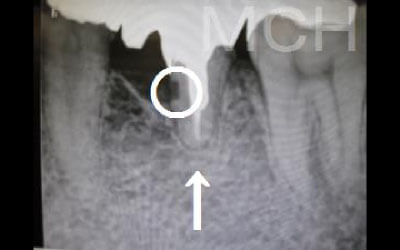

2 歯が傾いてくる、落ちてくる

歯は互いに支え合い、バランスを保っています。そのため、歯が抜けると支えがなくなり、抜けた部分の両隣の歯が傾いたり、上の歯が下に移動してきたりすることがあります。